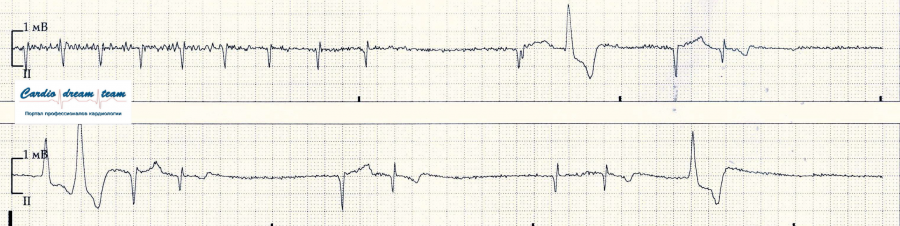

Утром при санировании интубационной трубки произошло её смешение. Спонтанного дыхания у больной почти нет. Пока переинтубация, развилась гиперкапния и гипоксия которая на ЭКГ проявилась таким ритмом.

Рвота у пациентки